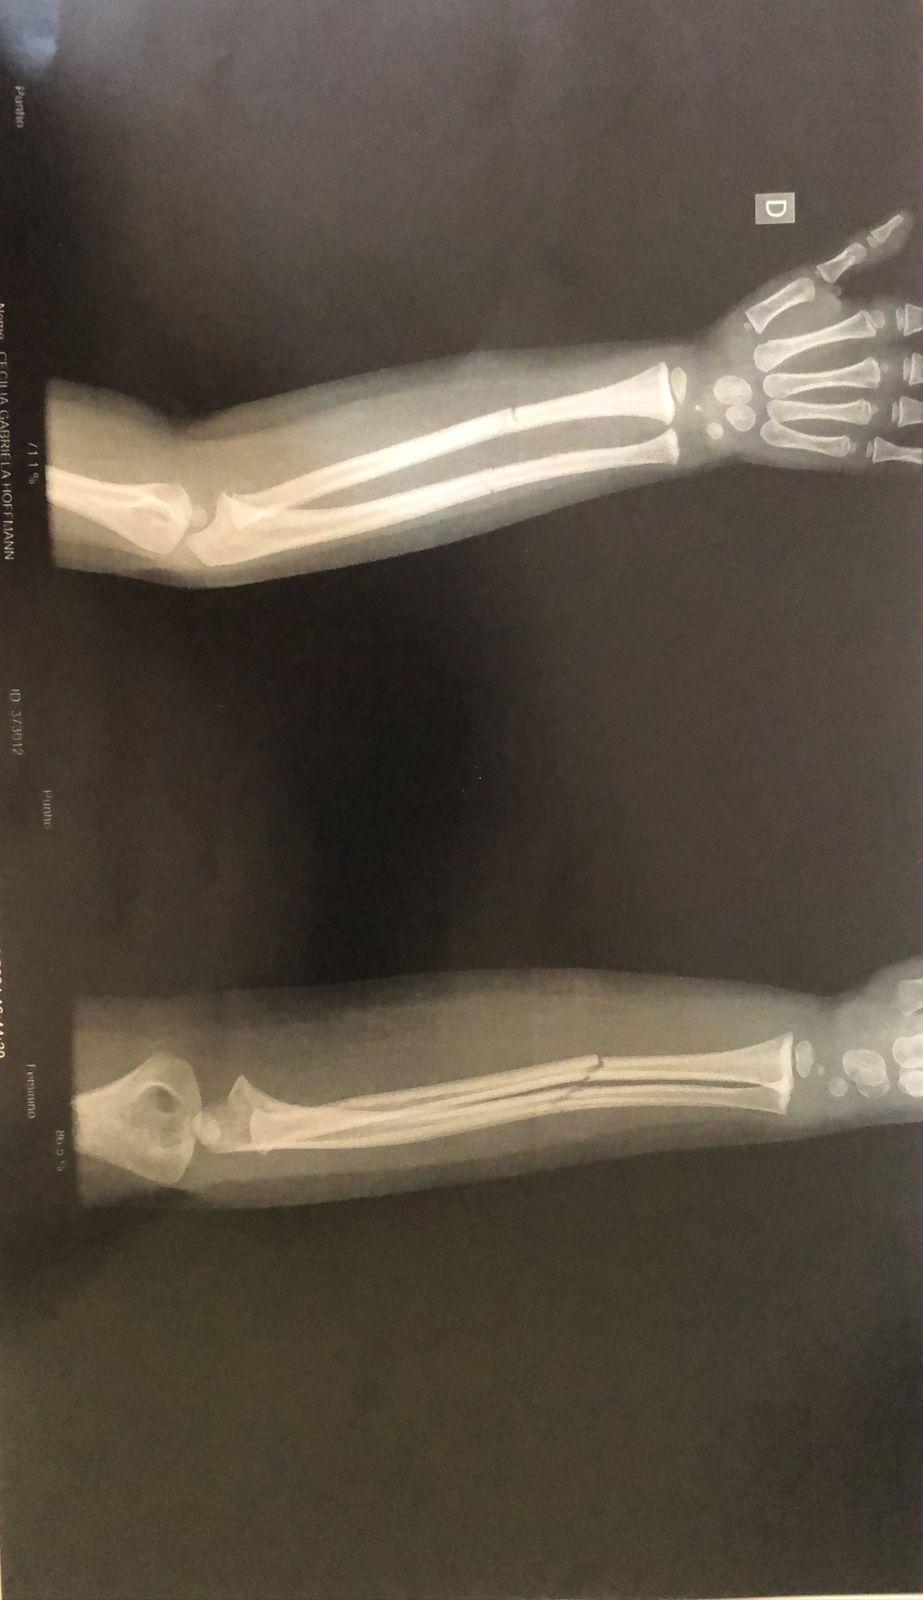

O resultado do exame (imagem acima) apresentou duas fraturas fechadas no braço da criança, que voltou para o hospital Bom Pastor após fazer o Raio-X, e ficou aguardando em um leito a transferência para algum hospital da região a fim de receber atendimento especializado.